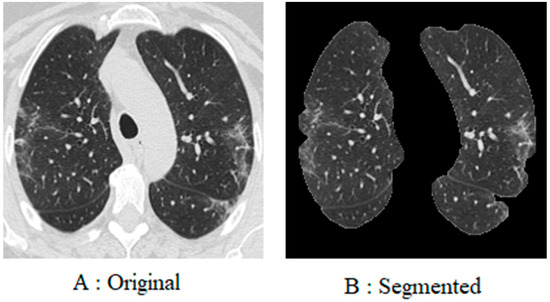

The suggested dataset (SARS-CoV-2) contains 2481 CT images shared among 1252 patients infected with COVID-19; and 1229 CT scans for non-COVID-19 patients that have other pulmonary diseases. Data were gathered from hospitals in Sao Paulo, Brazil. In this case, the data consist of 60 patients infected with coronavirus; 28 of them were female, and 32 were male [42]. The size of the images in this database was different; the size of all the images equalized before the pre-processing stage (Figure 2). The dimensions of the images vary; for example, the smallest size recorded in the database is 104 × 153, while the largest size is 484 × 416. Figure 3 displays several instances of CT scans from both SARS-CoV-2-infected and non-infected patients, which form part of the dataset.

Figure 2. Database sample images.

Fractalfract 08 00237 g002